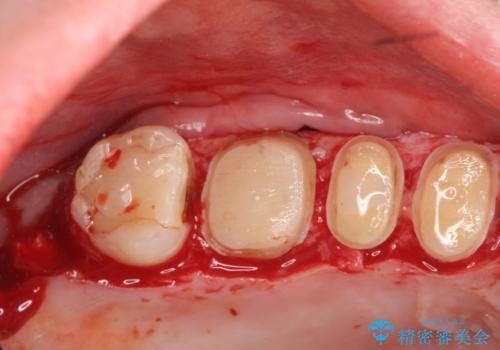

銀歯周囲の虫歯再発や、歯ぐきよりも深い虫歯、根尖性歯周炎と言った複合的な問題を、

歯周外科、精密根管治療、セラミック治療を行い、妥協のないセラミック治療を計画します。

今回の治療では歯ぐきの問題を解決するため、歯周外科を行いました。